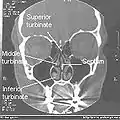

Normal Nose CT Front cross section

Coronal section of nasal cavities.